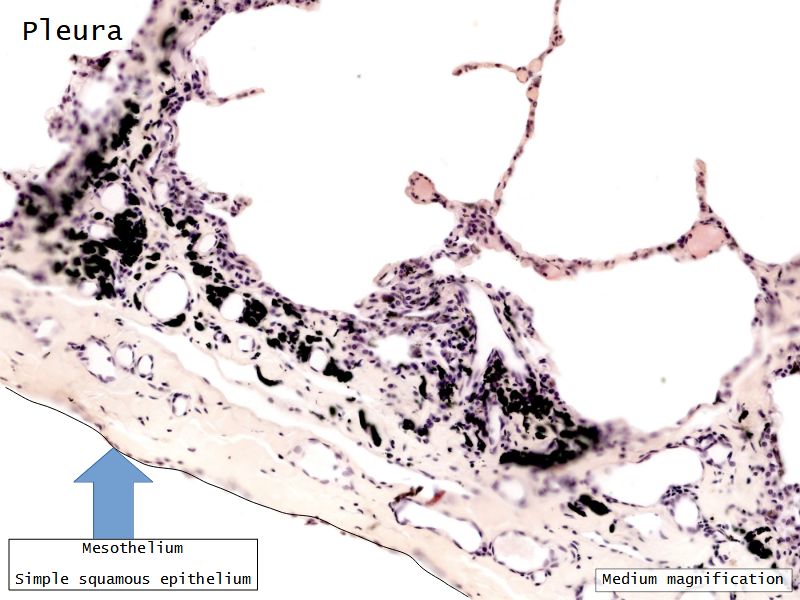

Fill in all the missing labels, and assess as you move through the slides. Answers on the down slide. It is important to do this using pen and paper, and not just glance through the images.